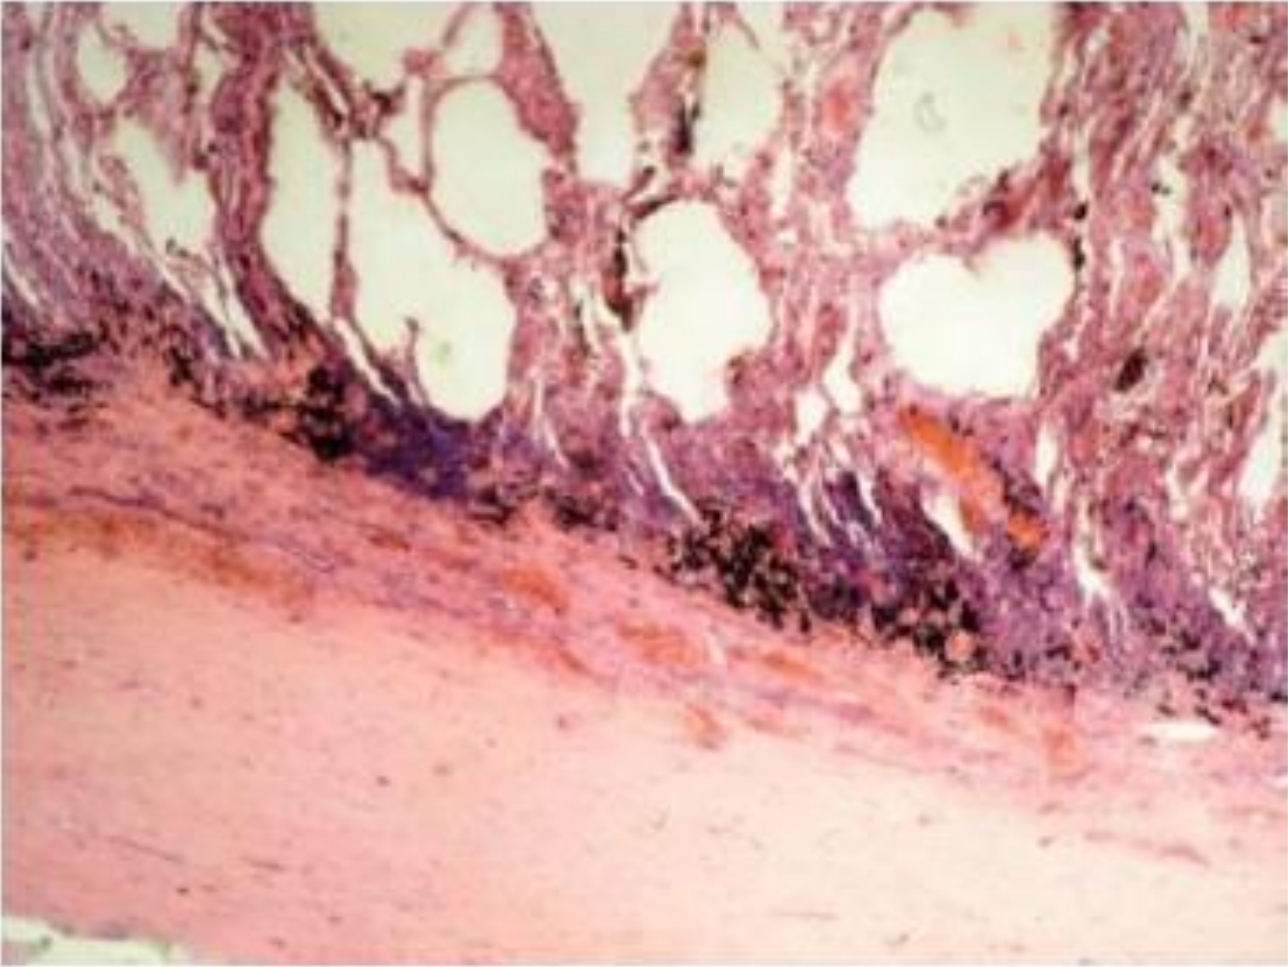

1. Haematoxylin and eosin

2. Lung with pleura

3. Pleura is thickened. Pink due to deposition of hyaline. Blood vessel wall is thickened. Lumen is narrow.

4. Hyalinosis of pleura

5. Exudative fibrinous inflammation and chronic inflammation